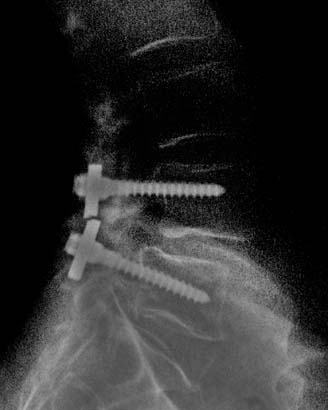

Sebelum

membahas James Burda, kita perlu ketahui dulu tentang chiropractor.

Yakni termasuk dalam pengobatan alternatif, yang mana berkonsentrasi

masalah penyembuhan dengan terapi pada tulang belakang, persendian, dan

jaringan lunak.

Kembali pada

kisah James Burda, ia mengaku memiliki keahlian chiropactor dan dapat

menyembuhkan segala penyakit dengan kekuatan yang diperolehnya: dari